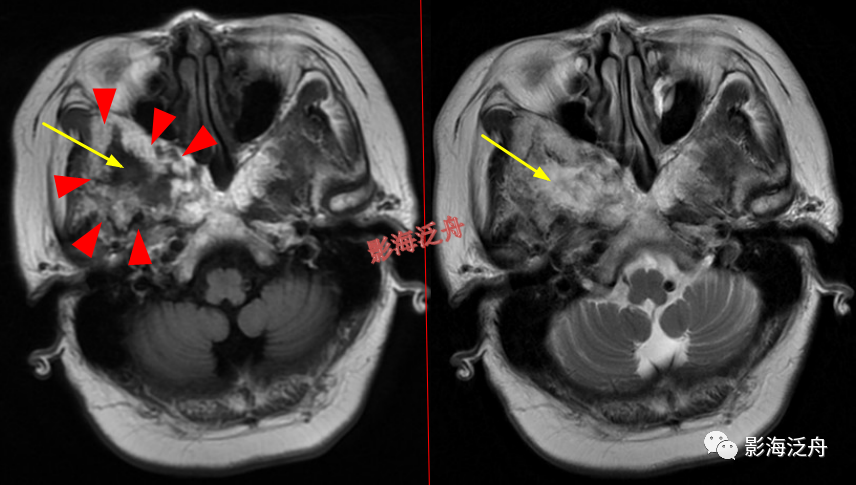

蝶骨骨纤维异常增殖症(红箭头),病灶内部可见特征性的囊变区(黄箭)。蝶骨的病变在MR上识别起来更为困难,因为蝶骨位于颅底部,此处骨骼、肌肉、脂肪等多种组织成分混杂,导致正常情况下也看起来非常乱。不要着急,慢慢学。

左侧顶骨骨纤维异常增殖症。病灶位于左侧顶骨板障区,局部骨质呈膨胀性改变,病灶边缘骨质硬化,呈明显低信号(红箭头),内部可见大片状絮状结构(黄箭)以及局灶性的玻璃样变性区(绿箭头)。